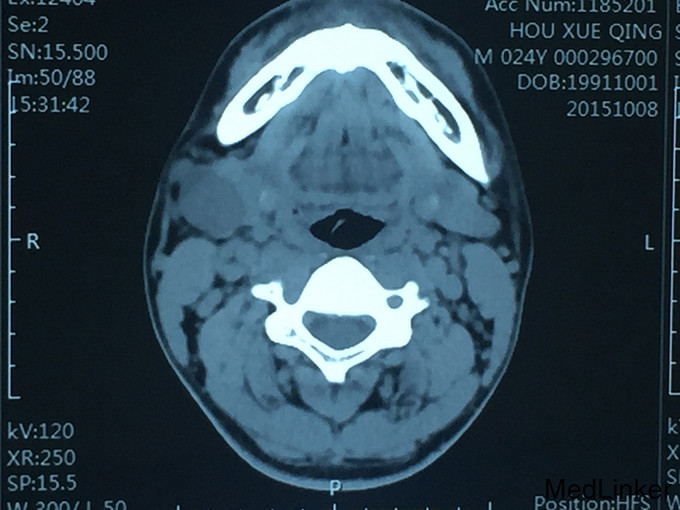

查体:右颌下区可扪及肿物大小约4*3*3cm,质地中等,活动,轻度压痛,和颌下腺相连,颌下腺导管口无红肿,分泌畅。 复查:CT:颌下腺多行性腺瘤可能

诊断:右颌下腺多形性腺瘤可能 治疗:全麻下右颌下腺及肿物切除,术中病理:右颌下腺多形性腺瘤